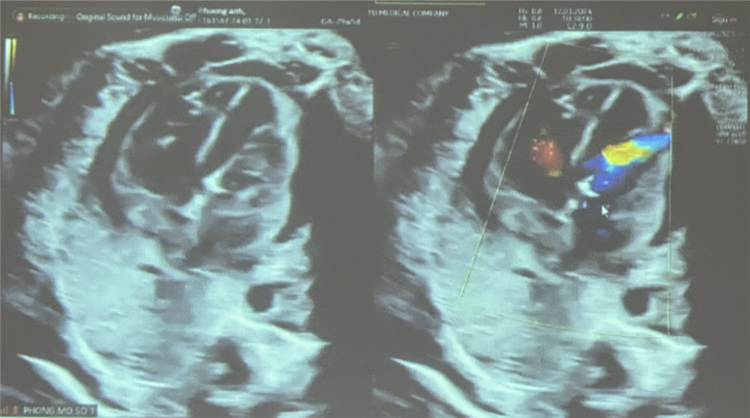

Siêu âm kiểm sau thực hiện can thiệp: luồng thông PFO shunt phải – trái, vận tốc qua van động mạch chủ 180 cm/s, không ghi nhận hở chủ |

Sau nong, kiểm tra dòng chảy qua van động mạch chủ lên tốt. Siêu âm kiểm sau thực hiện can thiệp: luồng thông PFO shunt phải – trái, vận tốc qua van động mạch chủ 180 cm/s, không ghi nhận hở chủ, nhịp tim thai 188 lần/phút, có tràn dịch màng ngoài tim nhẹ 4,5 mm.

Siêu âm kiểm sau thực hiện can thiệp: luồng thông PFO shunt phải – trái, vận tốc qua van động mạch chủ 180 cm/s, không ghi nhận hở chủ